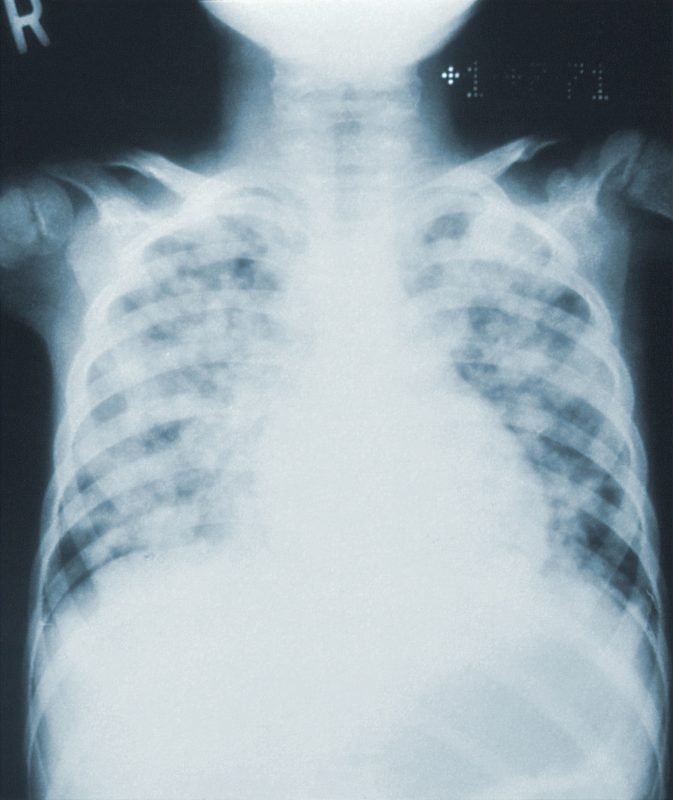

Um surto de pneumonia que já matou ao menos seis pessoas em uma clínica particular na província de Tucumán, na Argentina, pode ser causado por uma bactéria encontrada naturalmente em água doce. Os casos ganharam fama mundial no começo deste mês.

O surto parece, até agora, restrito a uma clínica privada da cidade de San Miguel de Tucumán, a 1.300 km de Buenos Aires. Dos 10 infectados, oito são profissionais de saúde.

De acordo com o site R7, no último fim de semana, autoridades sanitárias disseram que os casos foram causados por uma bactéria chamada legionela. Os profissionais trabalham para identificar a especificação da bactéria, embora haja uma forte suspeita de se tratar da Legionella pneumophila.

A Legionella pneumophila é uma bactéria do tipo bacilo Gram-negativo, que, segundo o Manual MSD de Diagnóstico e Tratamento, “frequentemente causa pneumonia”.

Este guia médico descreve a infecção por legionela como uma síndrome semelhante à gripe. Como sintomas os pacientes têm febre, calafrios, mal-estar, dor no corpo, confusão, náuseas, diarreia e dor abdominal.

Quando a doença evolui para a pneumonia, é comum haver falta de ar, dor no peito e que a pessoa cuspa bolas de sangue.

A bactéria não costuma ser transmitida entre pessoas, apesar de isso ser possível “em raras circunstâncias”, diz o CDC.

O Manual MSD ressalta que quando surtos ocorrem em hospitais, como na Argentina, “geralmente envolvem uma fonte de água quente contaminada”.